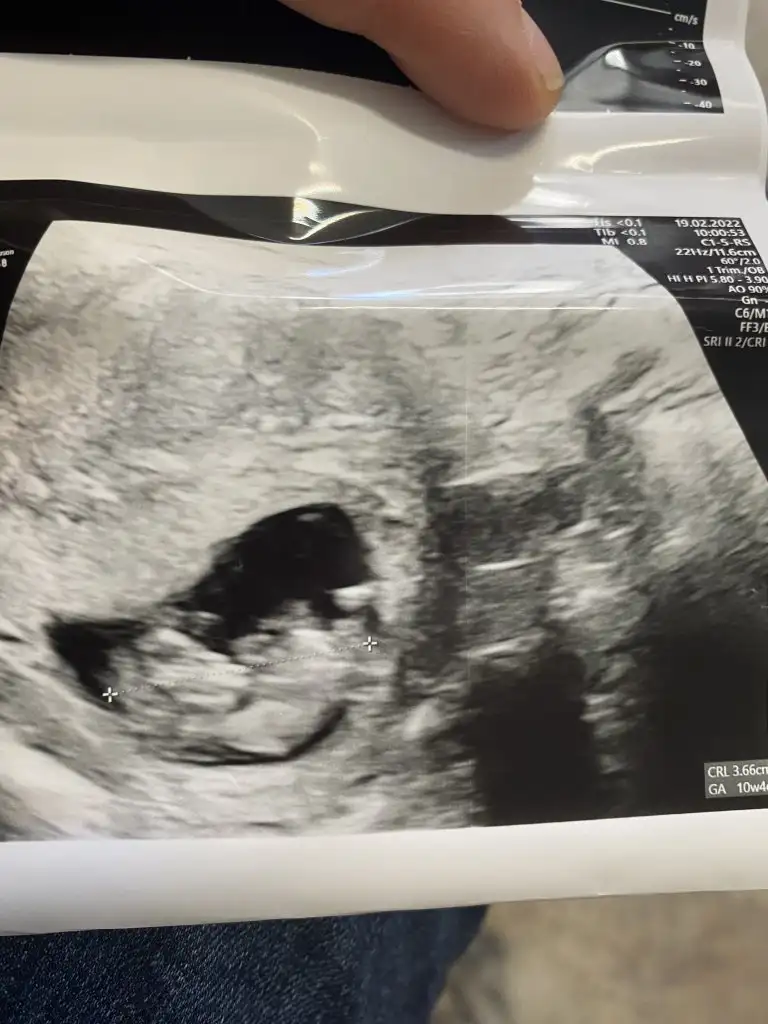

Canım benim düşük geçmişim var o nedenle her hafta kontrole gidiyorum ben, şuan bir risk yok çok şükür ama hamile olduğumu öğrendiğimde doktorumla bu şekilde anlaşmıştım. Tamamen meraktan yaniBugün tam 9 haftalık canım baya hareketliydi yaramaz bir oğlan gibi hissediyorumAramızda 5 gün varmış maşallah 12 haftalık olunca ikili tarama için çağırdı cinsiyet tahminide yapıcam o gün dedi Senide çağırdımı?

Aaaa bu minnos erkekTeyzeleri bizde büyümüşüzz kalbimizde maşallah çok kuvvetliydi bu defa 9 haftalığız bin şükürr çok duyguluydum ağladım bu sefer hareketlerinide görünceRabbim isteyen herkese nasip etsin bizlerede sağlıkla kucağımıza almayı nasip etsin